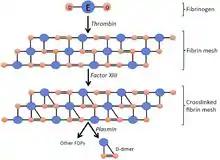

Pathophysiology

Blood has a natural tendency to clot when blood vessels are damaged (hemostasis) to minimize blood loss.[102] Clotting is activated by the coagulation cascade and the clearing of clots that are no longer needed is accomplished by the process of fibrinolysis. Reductions in fibrinolysis or increases in coagulation can increase the risk of DVT.[102]

The process of fibrinolysis, where DVT clots can be dissolved back into the blood, acts to temper the process of thrombus growth.[105] This is the preferred process. Aside from the potentially deadly process of embolization, a clot can resolve through organization, which can damage the valves of veins, cause vein fibrosis, and result in non-compliant veins.[106][107] Organization of a thrombus into the vein can occur at the third stage of its pathological development, in which collagen becomes the characteristic component. The first pathological stage is marked by red blood cells, and the second is characterized by medium-textured fibrin.[107]

Tissue factor, via the tissue factor–factor VIIa complex,[112] activates the extrinsic pathway of coagulation and leads to conversion of prothrombin to thrombin, followed by fibrin deposition.[86] Fresh venous clots are red blood cell and fibrin rich.[42] Platelets and white blood cells are also components. Platelets are not as prominent in venous clots as they are in arterial ones, but they can play a role.[56] In cancer, tissue factor is produced by cancer cells.[84] Cancer also produces unique substances that stimulate factor Xa, cytokines that promote endothelial dysfunction, and plasminogen activator inhibitor-1, which inhibits the breakdown of clots (fibrinolysis).[84]

D-dimers are a fibrin degradation product, a natural byproduct of fibrinolysis that is typically found in the blood. An elevated level[lower-alpha 6] can result from plasmin dissolving a clot—or other conditions.[113] Hospitalized patients often have elevated levels for multiple reasons.[39] Anticoagulation, the standard treatment for DVT, prevents further clot growth and PE, but does not act directly on existing clots.[114]